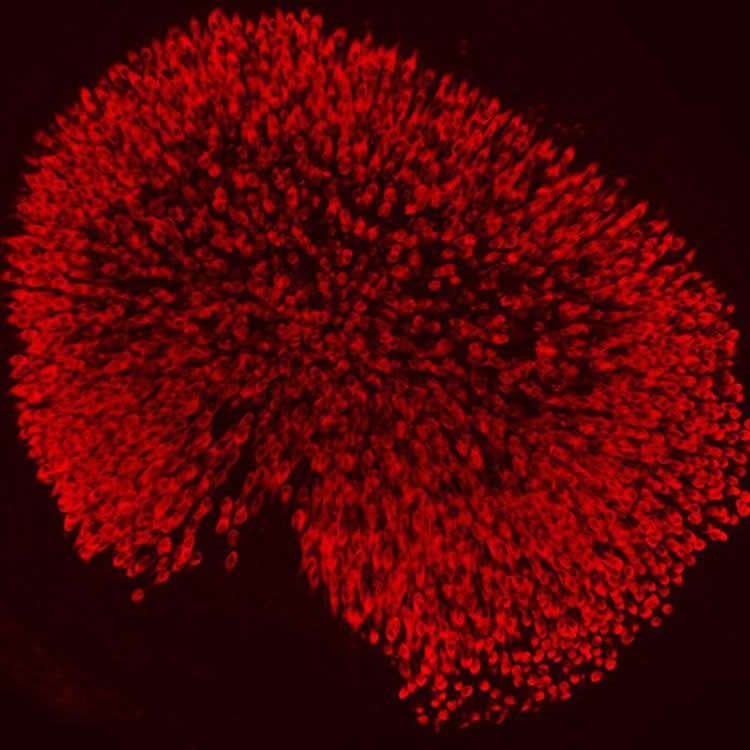

But scientists hope to find a way to regenerate these cells by examining how they develop in the first place. New research at Rockefeller University, in A. James Hudspeth’s Laboratory of Sensory Neuroscience, has identified two genes pivotal to the production of hair cells in young mice, who, just like human babies, lose the ability to generate these sensors shortly after birth. The study was published the week of October 26 in the Proceedings of the National Academy of Sciences.

First author, Ksenia Gnedeva, a postdoc in the lab, began by examining changes in gene expression in the utricle, a hair cell-lined organ within the inner ear that detects motion. She saw that the activity of two genes dropped dramatically shortly after the mice were born and hair cells ceased to develop in their utricles. These genes code for the proteins Sox4 and Sox11, which play a role in shaping the identity cells assume by regulating the expression of other genes.

Gnedeva tested these proteins’ involvement in hair cell formation by altering their expression. When both genes were shut down, she found that the entire inner ear, not just the utricle, developed abnormally. In other experiments, she turned on the genes in older mice whose hair cells were fully matured, and discovered that this gene activation could induce the production of new hair cells within a fully developed utricle.

Image Source: The images are credited to Laboratory of Sensory Neuroscience at The Rockefeller University/PNAS

Hair cells, the mechanosensory receptors of the inner ear, underlie the senses of hearing and balance. Adult mammals cannot adequately replenish lost hair cells, whose loss often results in deafness or balance disorders. To determine the molecular basis of this deficiency, we investigated the development of a murine vestibular organ, the utricle. Here we show that two members of the SoxC family of transcription factors, Sox4 and Sox11, are down-regulated after the epoch of hair cell development. Conditional ablation of SoxC genes in vivo results in stunted sensory organs of the inner ear and loss of hair cells. Enhanced expression of SoxC genes in vitro conversely restores supporting cell proliferation and the production of new hair cells in adult sensory epithelia. These results imply that SoxC genes govern hair cell production and thus advance these genes as targets for the restoration of hearing and balance.